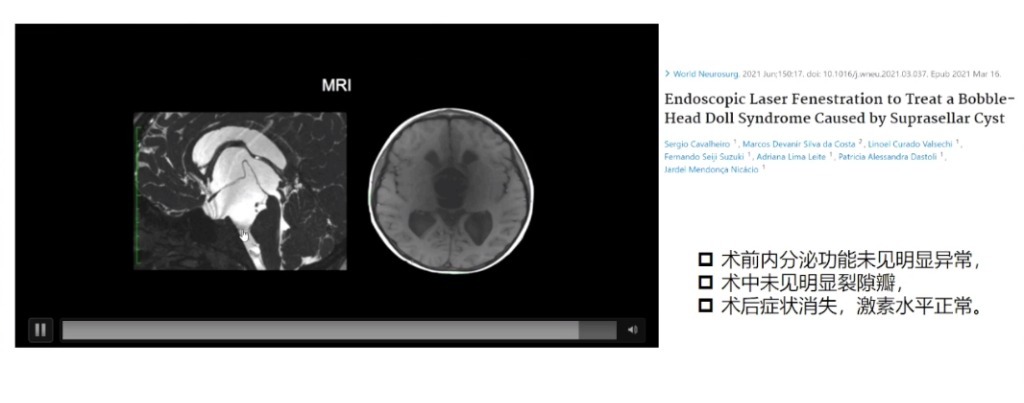

6.发现囊肿需要手术吗——对改善内分泌障碍效果需谨慎